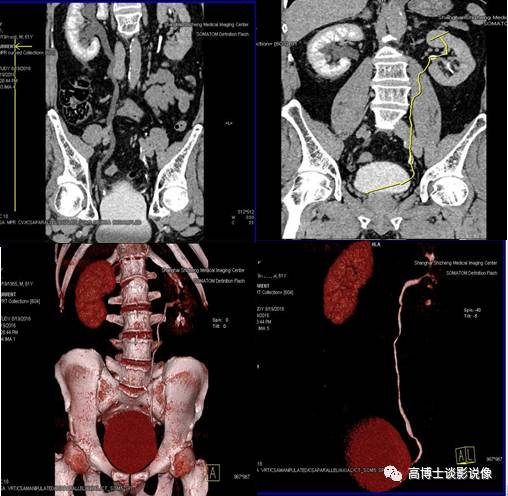

十、CT尿路造影VRT重建

CPR重建整体、全程显示输尿管结石及梗阻情况。去骨或非去骨VR重建,整体、直观显示整个泌尿系的轮廓、大体形态及梗阻情况,初步判断肾脏功能情况,同时整体显示全腹部动脉的走行、形态及有无异常。此例显示:右输尿管末端膀胱入口处结石伴右肾盂、右输尿管全程积水扩张,右肾显影功能延迟。